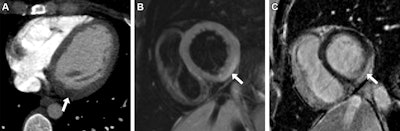

Acute myocarditis in a 30-year-old woman who presented to the emergency department with chest pain and an elevated troponin level. (A) Axial intravenous contrast-enhanced chest CT image acquired to rule out a pulmonary embolism shows focal myocardial low attenuation in the left ventricle basal inferolateral wall (arrow), indicating regional myocardial edema. (B) Short-axis 1.5-tesla T2-weighted cardiac MR image acquired 2 days later shows subepicardial hyperintensity (arrow), indicating acute myocardial edema. (C) Short-axis 1.5- tesla late gadolinium-enhanced cardiac MR image shows corresponding subepicardial late gadolinium enhancement (arrow), indicating inflammation.Acute myocarditis in a 30-year-old woman who presented to the emergency department with chest pain and an elevated troponin level. (A) Axial intravenous contrast-enhanced chest CT image acquired to rule out a pulmonary embolism shows focal myocardial low attenuation in the left ventricle basal inferolateral wall (arrow), indicating regional myocardial edema. (B) Short-axis 1.5-tesla T2-weighted cardiac MR image acquired 2 days later shows subepicardial hyperintensity (arrow), indicating acute myocardial edema. (C) Short-axis 1.5- tesla late gadolinium-enhanced cardiac MR image shows corresponding subepicardial late gadolinium enhancement (arrow), indicating inflammation. Images and caption courtesy of the RSNA.